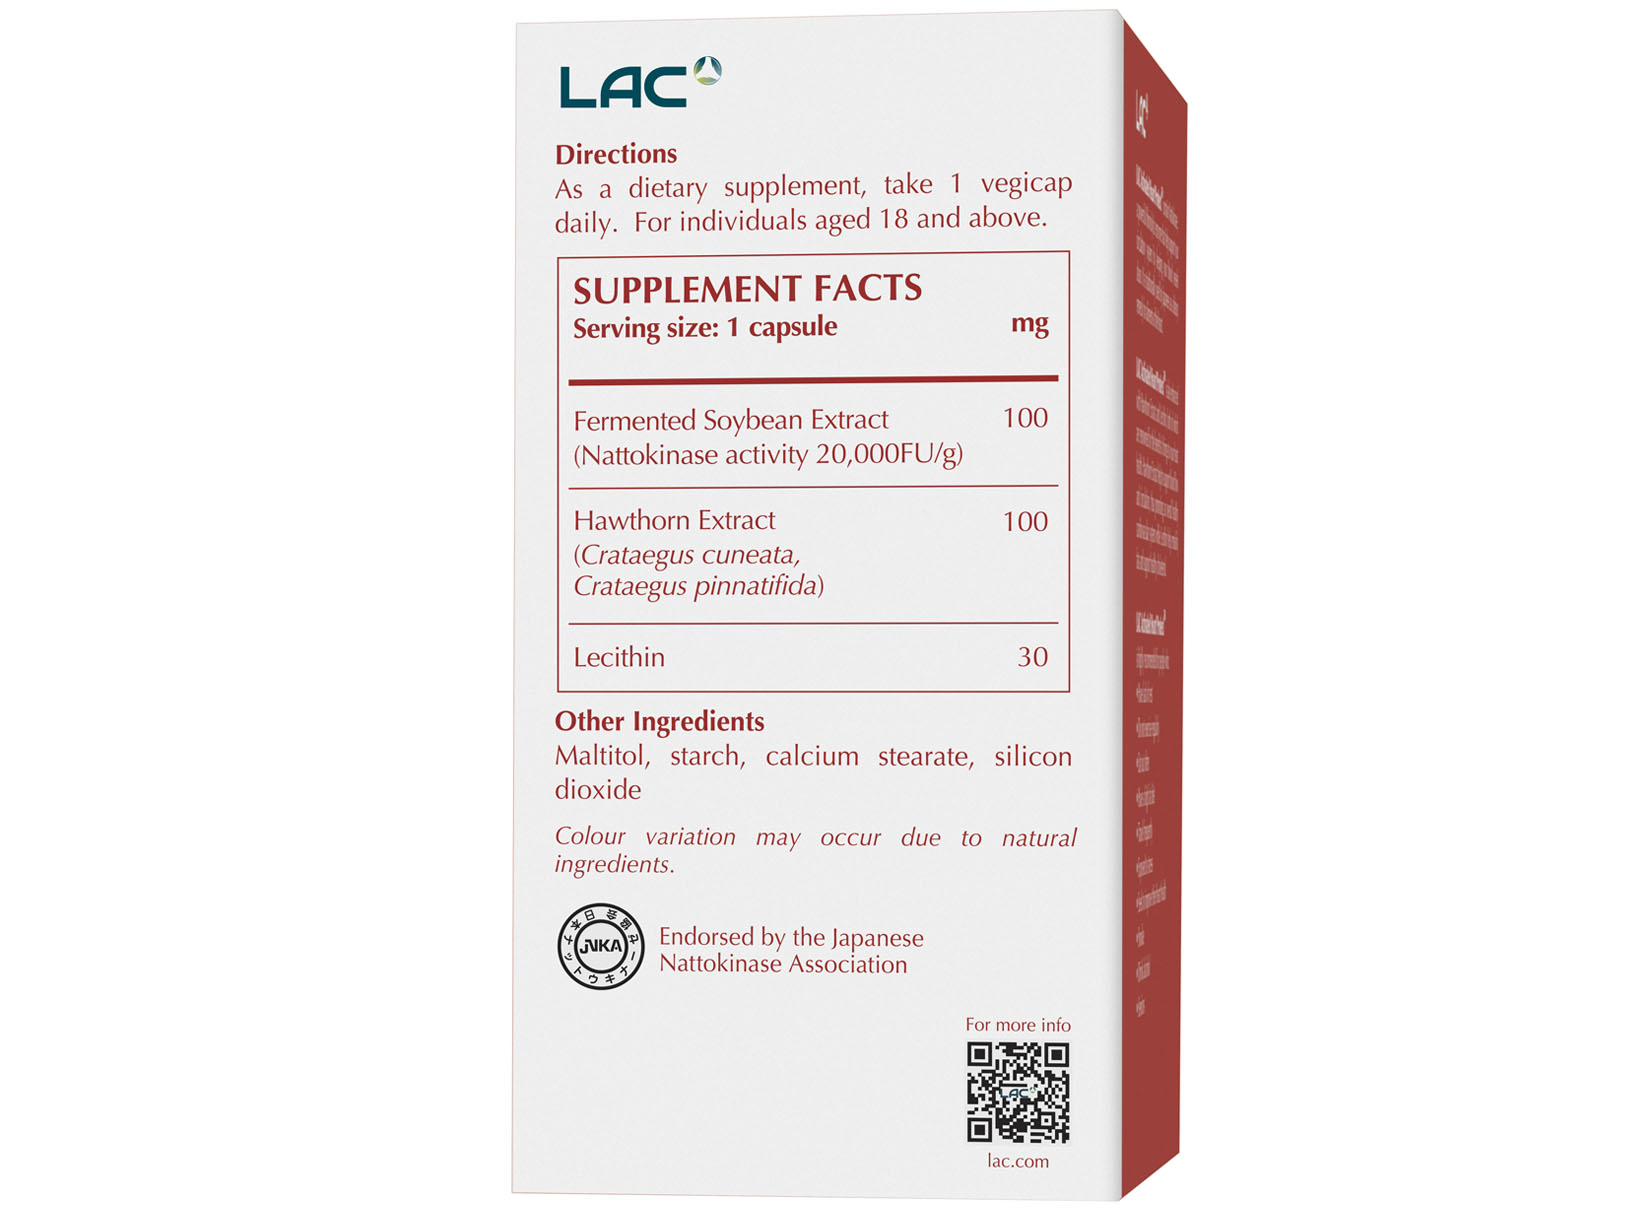

| Ingredients | Amount Per Serving |

| Fermented Soybean Extract

(Nattokinase Activity 20,000FU/g) |

100 mg |

| Hawthorn Extract (Crataegus cuneata, Crataegus pinnatifida) | 100 mg |

| Lecithin | 30 mg |

| Direction of Use | As a dietary supplement, take 1 vegicap daily. For individuals aged 18 and above. |

| Serving Size | 1 Vegicap |

| Servings per Container | 30 |

| Country of Origin | Manufactured in Japan |